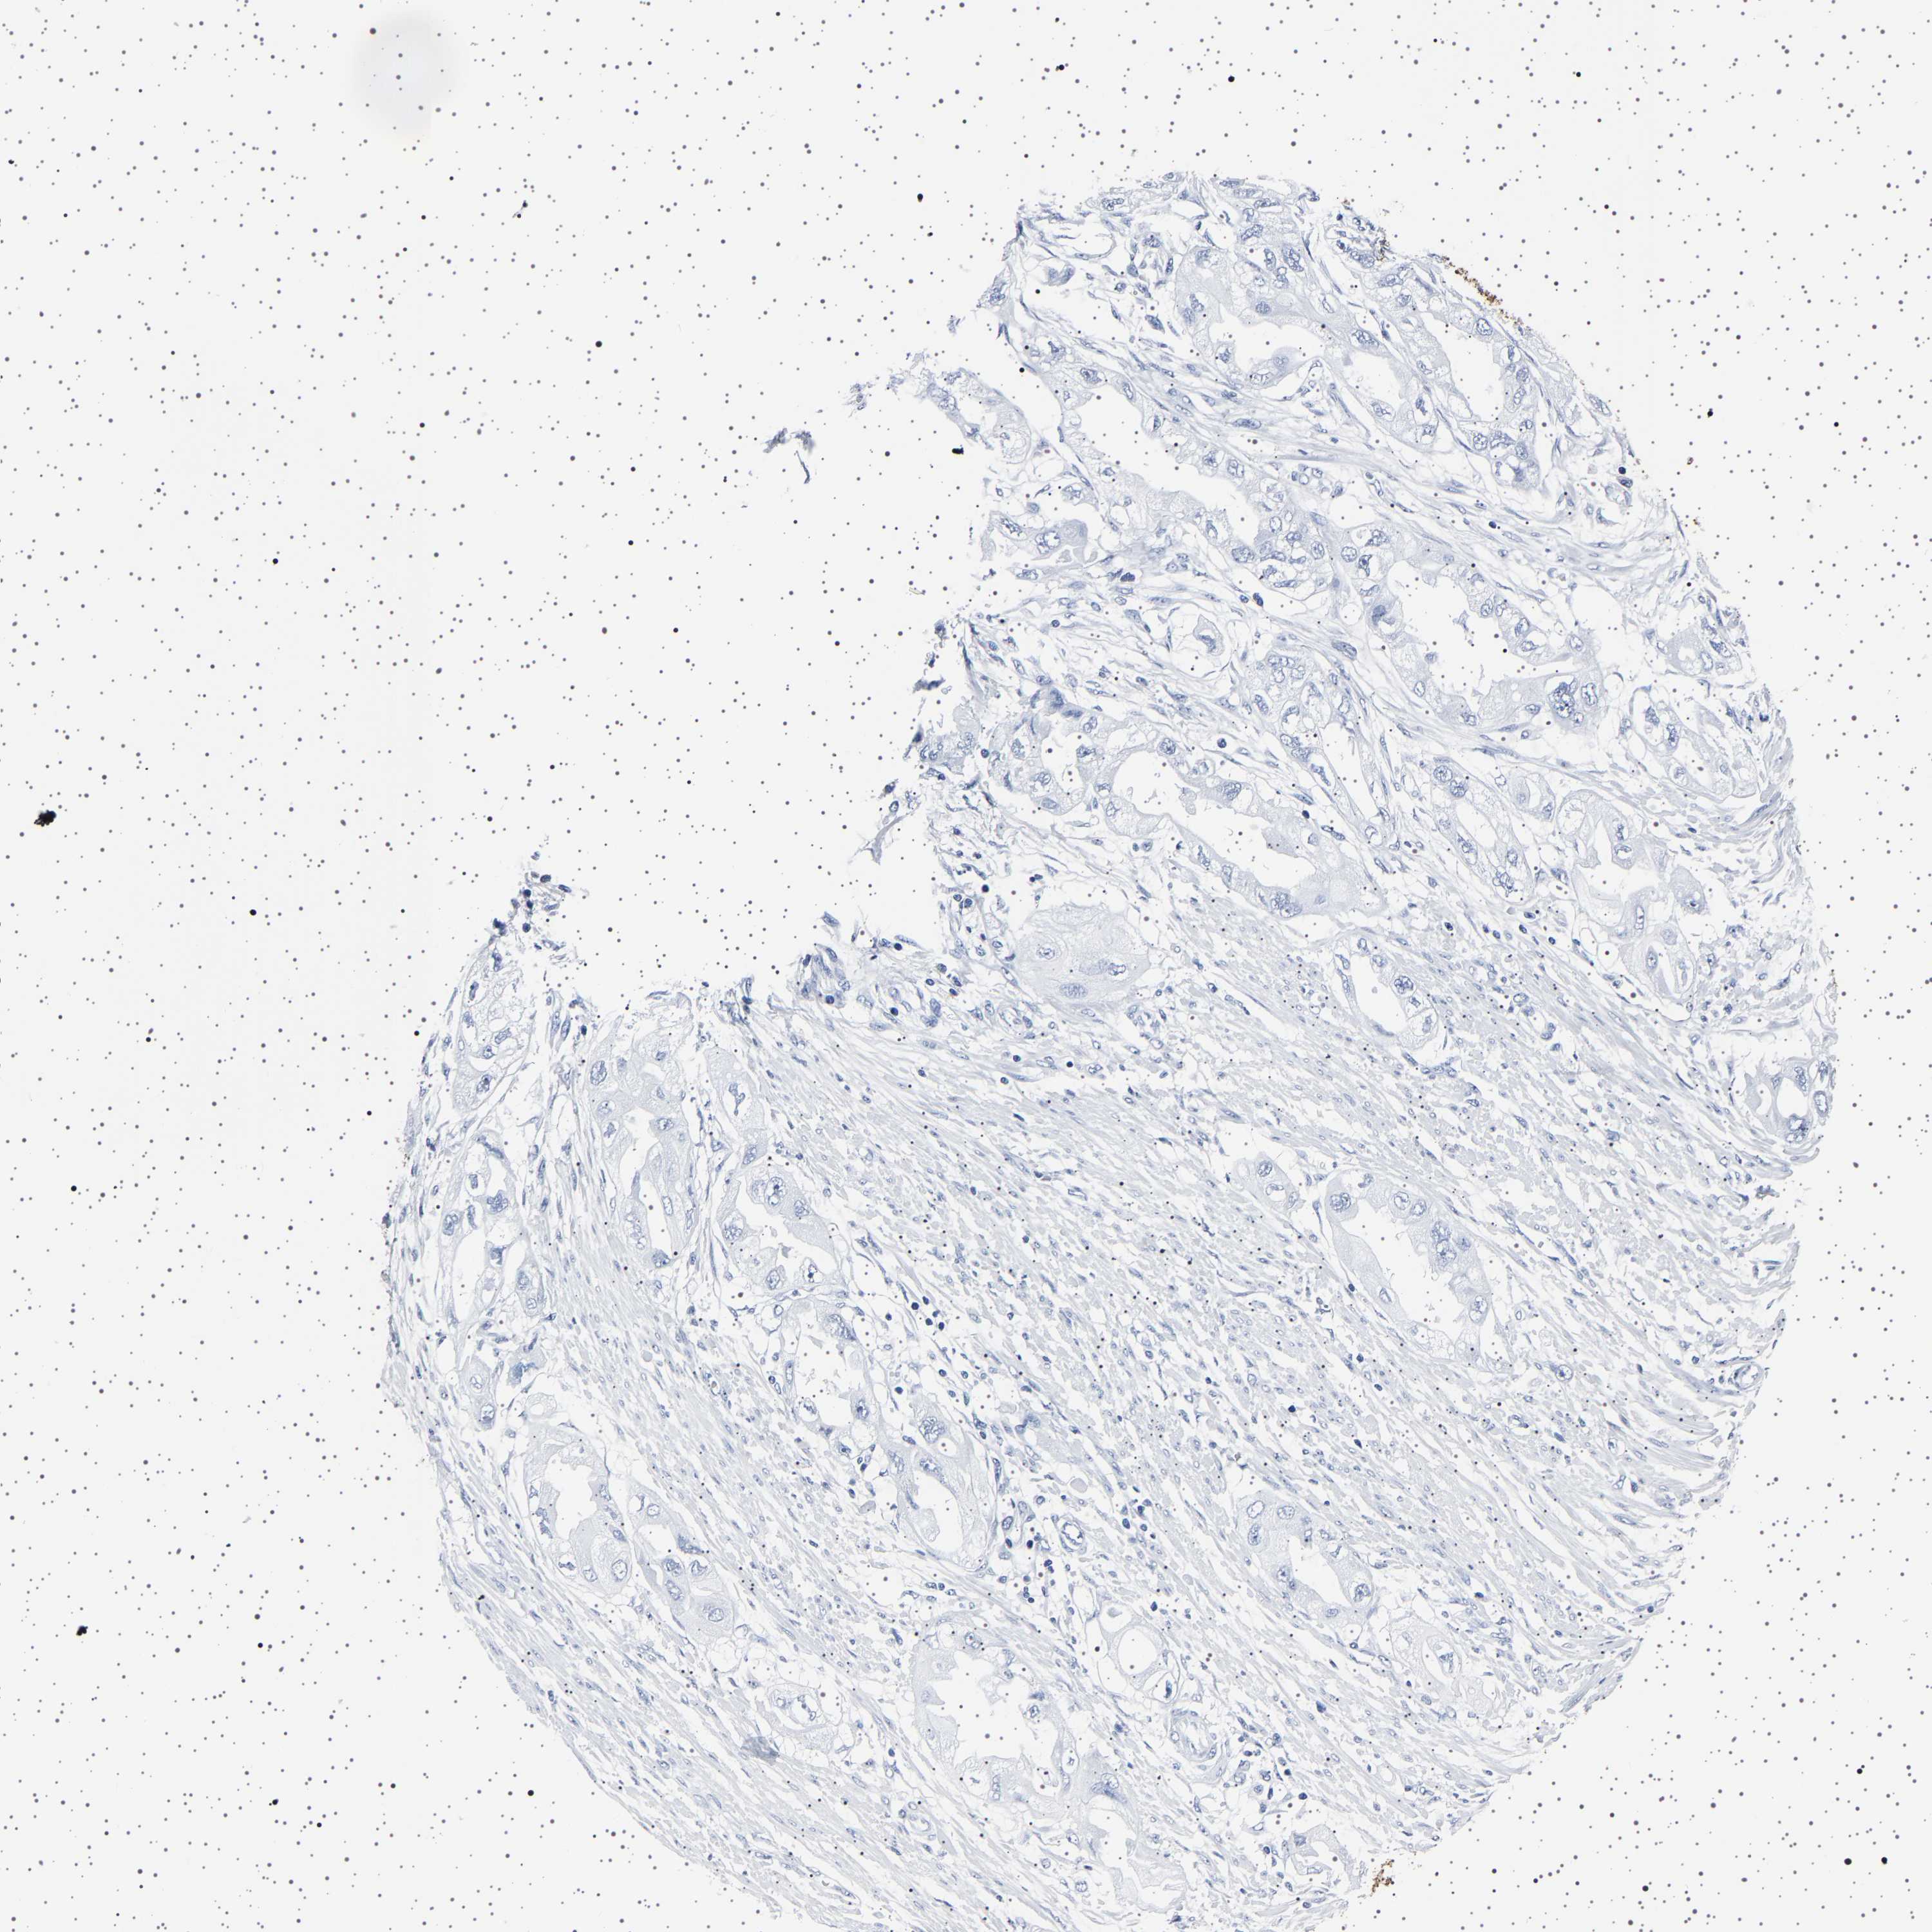

ENDOMETRIAL CANCER - Protein expressioni

A mouse-over function shows sample information and annotation data. Click on an image to view it in a full screen mode. Samples can be filtered based on level of antibody staining by selecting one or several of the following categories: high, medium, low and not detected. The assay and annotation is described here.

Note that samples used for immunohistochemistry by the Human Protein Atlas do not correspond to samples in the TCGA dataset.

Antibody stainingi

Antibody staining in the annotated cell types in the current human tissue is reported as not detected, low, medium, or high, based on conventional immunohistochemistry profiling in selected tissues. This score is based on the combination of the staining intensity and fraction of stained cells.

Each image is clickable and will lead to virtual microscopy that enables deeper exploration of all samples and also displays staining intensity scores, fraction scores and subcellular localization as well as patient and tissue information for each sample.

Antibody HPA035464

Antibody CAB020681

Staining

High

Medium

Low

Not detected

Intensity

Strong

Moderate

Weak

Negative

Quantity

>75%

75%-25%

<25%

None

Location

Nuclear

Cytoplasmic/membranous

Cytoplasmic/membranous,nuclear

Adenocarcinoma, NOS

Adenocarcinoma, metastatic, NOS

Neoplasm, malignant, NOS